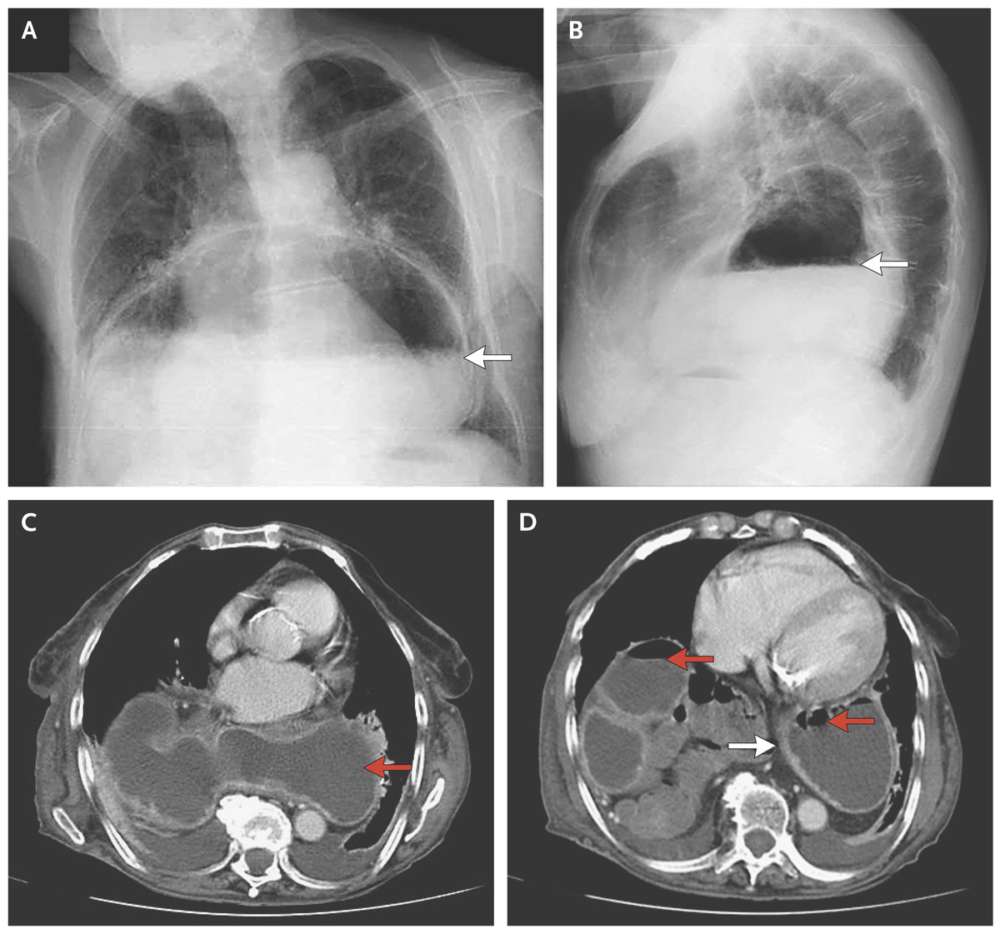

A chest radiograph showed a large air–liquid shadow in the inferior retrocardiac position (Panels A and B, arrows), which suggested a large paraesophageal hernia.

A computed tomographic scan showed a large retrocardiac mass containing air and liquid (Panels C and D, red arrows) that was consistent with herniation of the stomach into the chest.

Thickening of the gastric wall suggested edema (Panel D, white arrow) and compression of the first portion of the duodenum, which caused gastric distention.